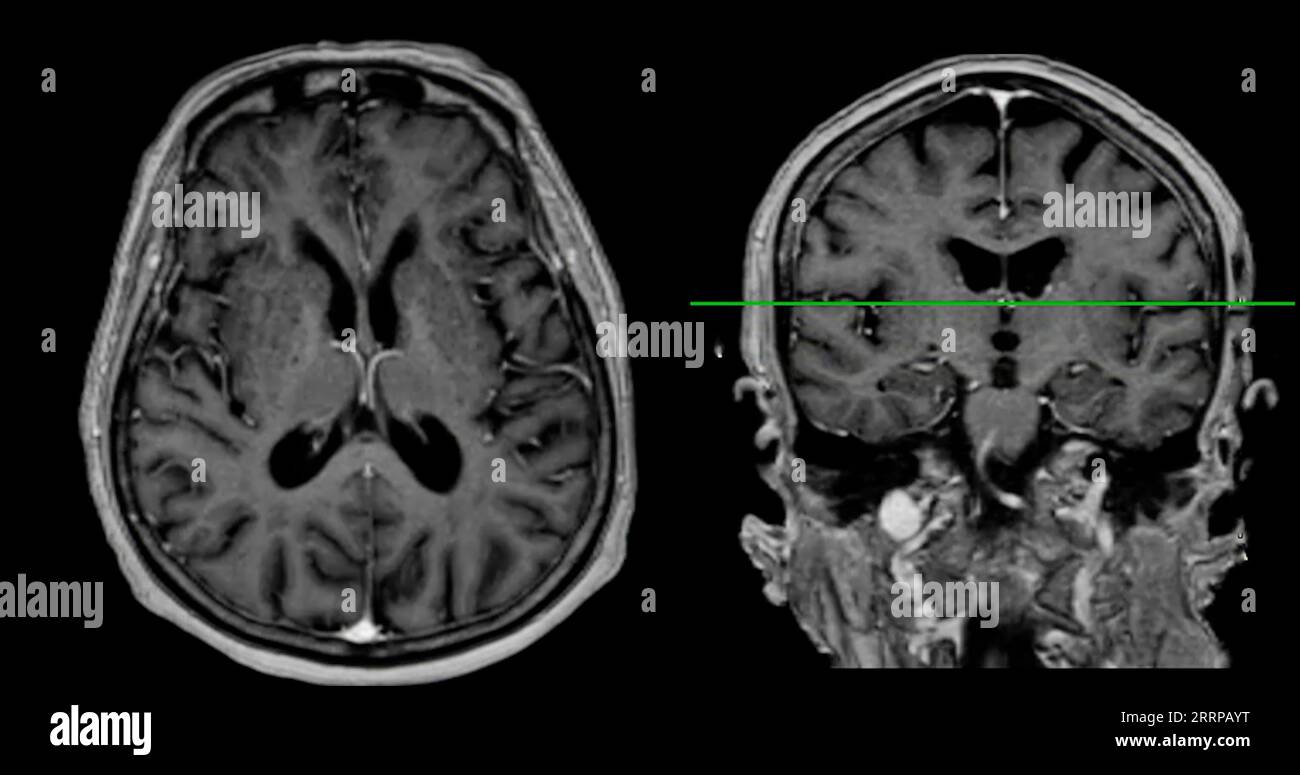

From www.alamy.com

MRI brain scan Axial and sagittal view with reference line for detect What Can Brain Mri Detect That Ct Cannot Bones, stones, blood, organs, lungs, cancer stages and abdominal emergencies. Ct scans are the most common. A variant called mr angiography (mra). An mri scan can be used to examine almost any part of the body, including the: Internal organs, such as the liver, womb. Where mri really excels is showing certain diseases that a ct scan cannot detect. Some. What Can Brain Mri Detect That Ct Cannot.

MRI brain scan Axial and coronal view with reference line for detect What Can Brain Mri Detect That Ct Cannot Mri can detect abnormalities that might be obscured by bone with other imaging methods. Understand their pros and cons along with general guidelines that doctors use to decide between head ct and mri. Where mri really excels is showing certain diseases that a ct scan cannot detect. In the case of brain imaging, mri provides highly accurate and detailed images. What Can Brain Mri Detect That Ct Cannot.